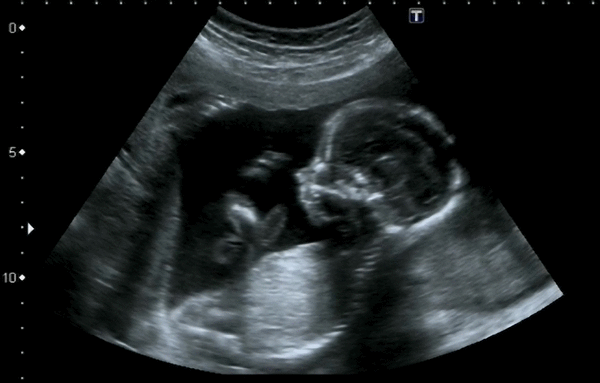

A Denver company has received federal approval to market an artificial intelligence program it says can predict when babies will arrive based on their ultrasounds, raising the possibility of flagging premature births.

Delivery Date AI predicts when a baby will be born, with an 11-day margin of error in either direction, based on second- and third-trimester ultrasounds.

The AI was trained on millions of ultrasound images from the University of Kentucky that had information about how long the pregnancy lasted, with the patients’ personal data removed.